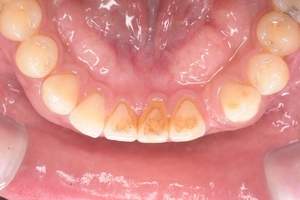

歯石除去

治療前

治療後

| 年齢 | 43歳・男性 |

|---|---|

| 主訴 | 歯石をとりたい |

| 治療内容 | 歯石除去 |

| 治療期間 | 30分 |

| 費用 | 約2,000円 |

| リスク・副作用 | ・歯ぐきの炎症が強いと歯石を取る際に出血することがあります ・処置後に歯がしみることがあります ・歯と歯の間に隙間ができるので、息が漏れ発音しにくいと感じることがあります ・歯ぐきの炎症が軽減すると歯ぐきが引き締まり、歯が長く見えることがあります |